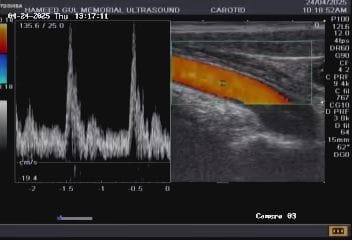

Vascular health: Carotid arteries, jugular veins, peripheral veins and arteries, abdominal aorta, and inferior vena cava.